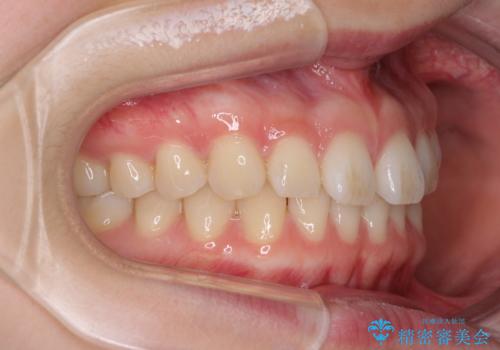

インビザラインによるすきっ歯の改善

- インビザライン

- 10ヶ月

下顎の歯列が強く上顎に咬みこむことで隙間ができてしまうため、マウスピースの保定装置では後戻りのリスクが高くなってしまいます。

そのため、上下ともに前歯の裏側を細いワイヤーで固定し、その上から保定装置のマウスピースを使用していただくこととしました。